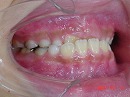

今回の症例写真は不正咬合の代表、 受け口<反対咬合> の改善症例です。

受け口 矯正前 矯正1年後

期間は1年6カ月で治療方法は独自の方法です。